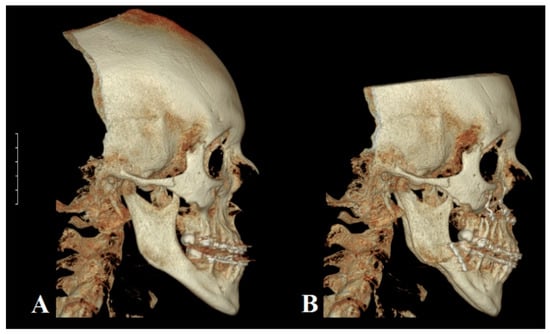

Morphometric analyses of facial profile provide information about potential gnathic defect in patients. Specifically, the concave profile, protrusion, and extension of the lower facial area are measured [79]. In extreme cases, long face syndrome can appear as part of the class III malocclusion phenotype [80], where the relationship between the upper and lower lip is distinctly disturbed. Due to an average 2 mm retrusion and potential atrophy of the upper lip, the eversion of the lower lip, difficulties with proper lip contact, or even a lack of connection between them may be observed [81]; these additionally reduce chin prominence and decreasing of depth of labiomental fold [80]. MP is manifested on the midface, and the paranasal area, nasolabial fold, and cheek line are flattened [7]. Due to the complex nature of the stomatognathic system, each growth irregularity forces changes within teeth position and thus occlusal status. During intraoral inspection, angle class III and canine class III with negative incisional overjet and reduced overbite are observed [74]. Moreover, open bite (anterior or complex) and cross bite (unilateral or bilateral) may be accompanied in the clinical image of MP. Interestingly, the occurrence of any dentofacial abnormalities leads to the activation of a compensatory mechanism aimed to restore functional balance within the orofacial region. Therefore, lower incisors are predominantly retroclined against proclined maxilla incisors. Additionally, modifications of the symphysis region and increased incisor eruption level may disproportionately compensate within the vertical dimension [82]. The potential coexistence of maxilla hypoplasia with MP may aggravate the abovementioned symptoms and clinical manifestations of class III skeletal malocclusion due to the posterior position of the upper jaw (Figure 1). Isolated maxilla deficiency can phenotypically provide similar features despite correct physiological mandibular proportions. It is worth noting that the skeletal conditioning of class III malocclusion may be ethnically different. It has been reported that in US population class III malocclusion mostly occurs as a maxillary hypoplasia and protrusion. In contrast, in Asians, this deformation is predominantly diagnosed with a normal upper jaw and the overgrowth of the mandible [83,84]. To avoid the misdiagnosis of improper upper jaw or mandible development, a lateral cephalometric radiograph with cephalometric analysis should be performed [84]; this is a standardized orthodontic method and a part of the diagnostic process of malocclusion and treatment planning. Angular and linear measurements carried out on a radiograph allow for the assessment of the positions of various anatomical structures [85]. Despite only analyzing skeletal relationship in the sagittal plane, this strategy determines which anomalies, dental or skeletal, underlie the disorder [86]. Angular and linear measurements carried out on a radiograph allow one to assess the anterior or posterior position of both jaws in relation to the anterior cranial base (Figure 2) [87]. A position on a cephalometric X-ray is marked by a line running from point S (midpoint of sella turcica; sella) to N (anterior end of nasofrontal suture, nasion). In turn, the localizations of the maxilla and mandible is indicated by point A (the most posterior point on the premaxilla in the midline and below anterior nasal spine; Subspinale) and point B (the deepest point in a fossa above chin; Supramentale), respectively [88]. Therefore, the value of angle between the SN and NA planes provides information regarding the sagittal position of the upper jaw in reference to the cranial base (82 ± 3°). In addition, the size of the angle created by the SN and NB allows one to lines assess the antero–posterior position of the mandible in comparison to the anterior part of the skull base (80 ± 3°) [89]. Both angles are recommended for measurements of retrognathism and MP in clinical practice [87]. Moreover, the evaluation of the mutual locations of mandible and maxilla plays a pivotal role in diagnosis and treatment planning as well. This relationship shows an ANB angle with a value for class I malocclusion from 0° to 4°. Thus, class II and III may be diagnosed when the value of ANB is above 4° and less than 0°, respectively. It is noteworthy that Wits appraisal, as a distance between point A and B projected onto an occlusal plane, may be also valuable for proper malocclusion diagnosis [90]. Physiological class I is in the range from −2 to 2 mm. Class II and III have Wits values of over 2 mm and less then −2 mm, respectively [91]. All of the abovementioned values have been presented according to Segner–Hasund’s cephalometric analysis [92].

Figure 1.

Representative 3D reconstructions of cone beam computed tomography (CBCT) examinations. Patient was diagnosed with class III skeletal malocclusion. (A) CBCT performed during pre-surgical orthodontic treatment. (B) Postsurgical treatment CBCT. The Le Fort I osteotomy of maxilla and the bilateral sagittal split osteotomy of mandible have been performed. The protrusion of maxilla and the retrusion of mandible were conducted to restore proper occlusal status. Osteosynthesis elements are visible (white) within both jaws.